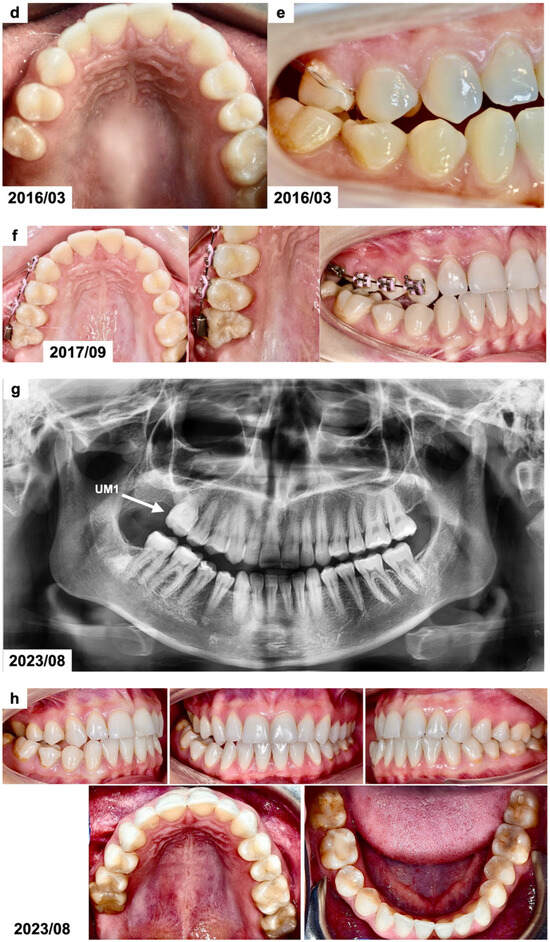

Figure 1.

(a) Intraoral photographs before surgical and orthodontic treatment. The patient was 8 years and 10 months old. (b) Panoramic radiograph before the treatment, presenting the odontogenic tumor in the left mandible molar region (OCx = complex odontoma). The patient was 8 years and 10 months old. (c,d) Intraoral photographs taken during the surgical removal of the tumor exposing the occlusal surface of the permanent lower left first molar (OCx = complex odontoma, LM1 = lower left first permanent molar). The patient was 8 years and 11 months old. (e) Panoramic radiograph after the surgical treatment and bonding of the orthodontic attachment (OA = orthodontic attachment). The patient was 8 years and 11 months old. (f) Panoramic radiograph 1 year after the removal of the tumor showing the orthodontic attachment bonded to the occlusal surface of the permanent lower left first molar (OA = orthodontic attachment). The patient was 10 years and 1 month old. (g) Intraoral photographs of spontaneously erupted permanent lower left first molar after removal of the orthodontic attachment. The patient was 10 years and 11 months old. (h) Panoramic radiograph 4 years after the surgical and orthodontic treatment (LM1 = lower left first permanent molar). The patient was 12 years and 7 months old. (i) Intraoral photographs 4 years after the surgical and orthodontic treatment showing the erupted permanent lower left first molar and its position in the dental arch. The patient was 12 years and 7 months old.

The lower removable plate with an extension to attach the elastic from the button bonded on the exposed impacted molar was prepared in March 2020. However, due to the eruption of the COVID-19 pandemic, it was not delivered to the patient after surgery. The university clinic was only treating emergencies for the next few months, and the patient came back after 1 year, in February 2021. The patient reported a spontaneous eruption of the impacted maxillary. The occlusal surface of the lower left first permanent molar with a bonded button was visible during the clinical examination. The panoramic radiograph (Figure 1f) revealed a distinct occlusal movement of the impacted tooth and normal healing after the removal of the tumor. In December 2021, the mandibular left first permanent molar erupted in the oral cavity (Figure 1g). No pathologies were present on the panoramic radiograph except for the bending of the distal root of the affected molar. The patient has received an activator with an expansion screw to correct his Class II relations and maxillary crowding. In August 2023, the impacted molar tooth erupted into occlusion, and the root development was finished (Figure 1h,i). A marked dilaceration of its distal root could be noticed, which was caused by the presence of a tumor in proximity to the developing, neighboring first molar. The prognosis of the affected molar was estimated as favorable in the long term if good oral hygiene is maintained. A complete regeneration of the alveolar bone defect was also seen. No other permanent molars on the side of the tumor were present on the radiograph. Orthodontic treatment with a removable appliance is continued.